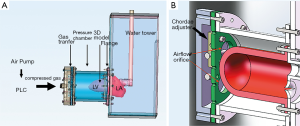

The MCS was powered by an air compressor (Figure 3), and a programmable logic controller (PLC) was used to control the driver. The compressed gas generated by the air pump was transferred to a pressure cell surrounding the flexible 3D model to make it contract and relax rhythmically. A pressure-elevating water tower was used as the systematic compliance component to simulate afterload in systole. The MCS generated a maximum systolic pressure of 107 mmHg, which is near physiological conditions. To simulate in vivo blood flow resistance, solutions with a viscosity similar to blood (~3.5–4.5 mPa/s) were also needed. Water, glycerol, dextran, and surfactants were mixed as the substitute. Nylon scattering particles with a diameter of 5 µm were also added for better echographic imaging. After being combined with the MCS, the flexible 3DP model of the MV could open and close in vitro as it does in vivo.